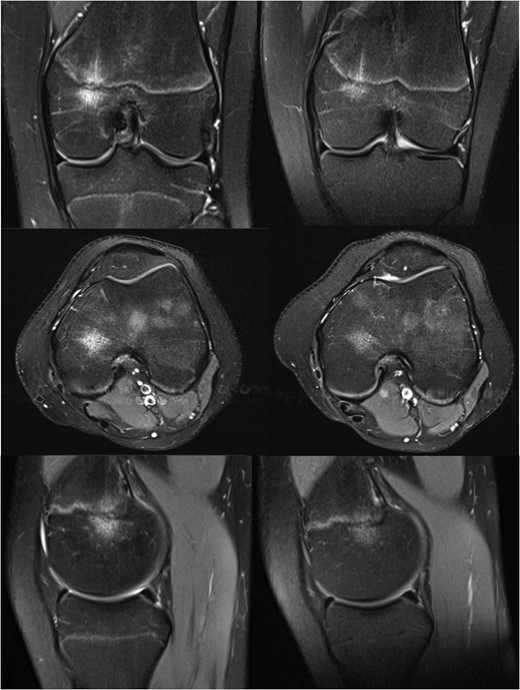

MRI images of the knee at 9 (left) and 13 months (right) after initial injury.

Her symptoms gradually improved without treatment, and with the significant improvement seen on her MRI scan she was eventually discharged from our care fourteen months after her initial injury.